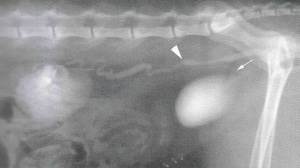

Рентген с контрастом также может использоваться, но такая процедура более инвазивна. В некоторых специализированных ветеринарных клиниках может быть доступна компьютерная томография. Снимки компьютерной томографии позволяют поставить очень точный диагноз. Другие методы, такие как уретроцистоскопия, влагалищная уретрография и выделительная урография, могут помочь визуализировать анатомические патологии и места выходов мочеточников в мочевом пузыре, уретре, влагалище или